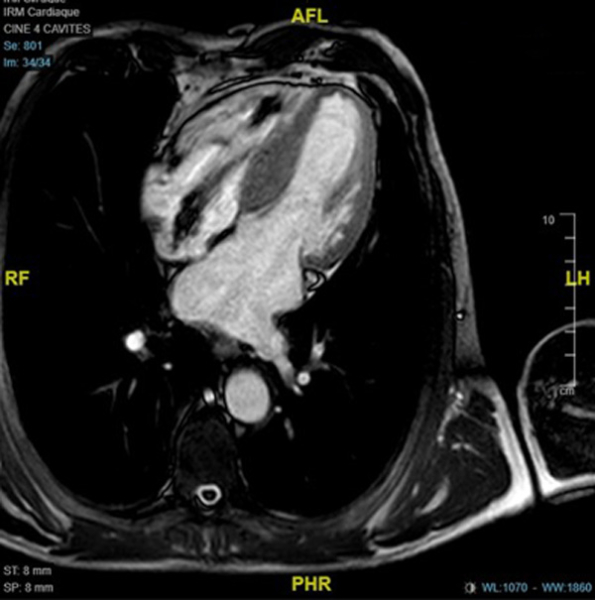

IRM

Figure 5

Figure 6

Figure 7

Figure 8 : Cartographie T1 N = 1000ms sur l’IRM 1,5 T

Conclusions de l’IRM :

- Cardiomyopathie hypertrophique asymétrique à prédominance septale (épaisseur maximale 19mm), sans atteinte VD

- Cinétique segmentaire homogène

- Zone de fibrose punctiforme inféro-septo-médiale isolée

- Absence d’allongement du T1